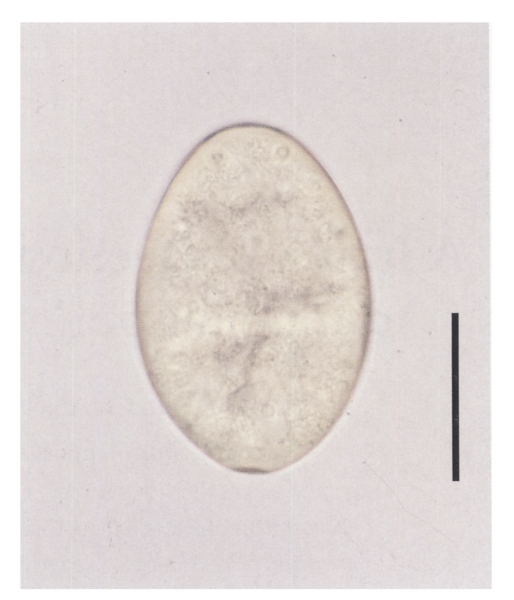

She had worked in a small restaurant, and had eaten raw frog meat several times about two months before onset of her symptoms. She denied ever eating freshwater fish in raw. Laboratory data were not available. A stool examination revealed six echinostome eggs, but none were found in family members. The eggs were bright yellow, elliptical, thin shelled with a shallow operculum, and measured 114.1 (111.2-118.6) µm long and 76.7 (74.1-79.0) µm wide (

Fig. 2).

Fig. 2An egg of Echinostoma hortense from the patient. Bar = 54 µm.